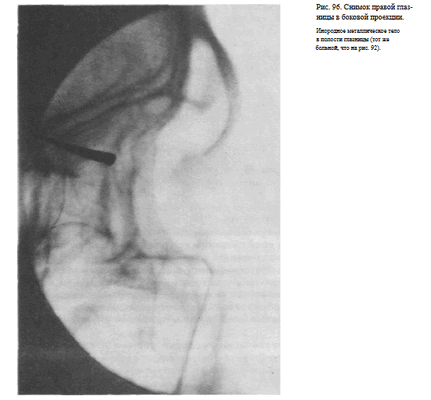

СНИМОК ГЛАЗНИЦЫ В БОКОВОЙ ПРОЕКЦИИ

Назначение снимка — отображение наружного края, верхней и нижней стенок глазницы, а также выявления инородных тел, находящихся в ее полости.

Укладка больного для выполнения снимка такая же, как для выполнения снимка черепа в боковой проекции (рис. 95).

Кассету размером 13X18 см устанавливают в кассетодержателе в поперечном положении. Наружный край глазницы соответствует центру кассеты, и на него направляют пучок излучения.

Информативность снимка. На снимке хорошо видна наружная стенка глазницы. Для выявления небольших участков измененной костной структуры других стенок информативность снимка, как правило, невысокая из-за суперпозиции анатомических образований противолежащей стороны лицевого скелета. Хорошо видны на снимке в данной проекции инородные тела (рис. 96).